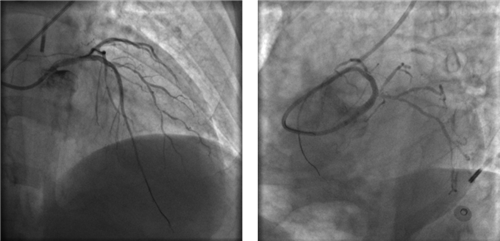

左冠血流保持通暢

確認(rèn)左冠血流保持通暢,大家懸著的心才稍稍放下。

根據(jù)IVUS檢查結(jié)果,在前降支近中段至左主干植入3枚支架,充分?jǐn)U張后,狹窄完全解除,血流恢復(fù)通暢。

植入3枚支架,血流恢復(fù)通暢

胡女士全程生命體征平穩(wěn),無慢血流、惡性心律失常等情況發(fā)生,她又一次闖關(guān)成功!